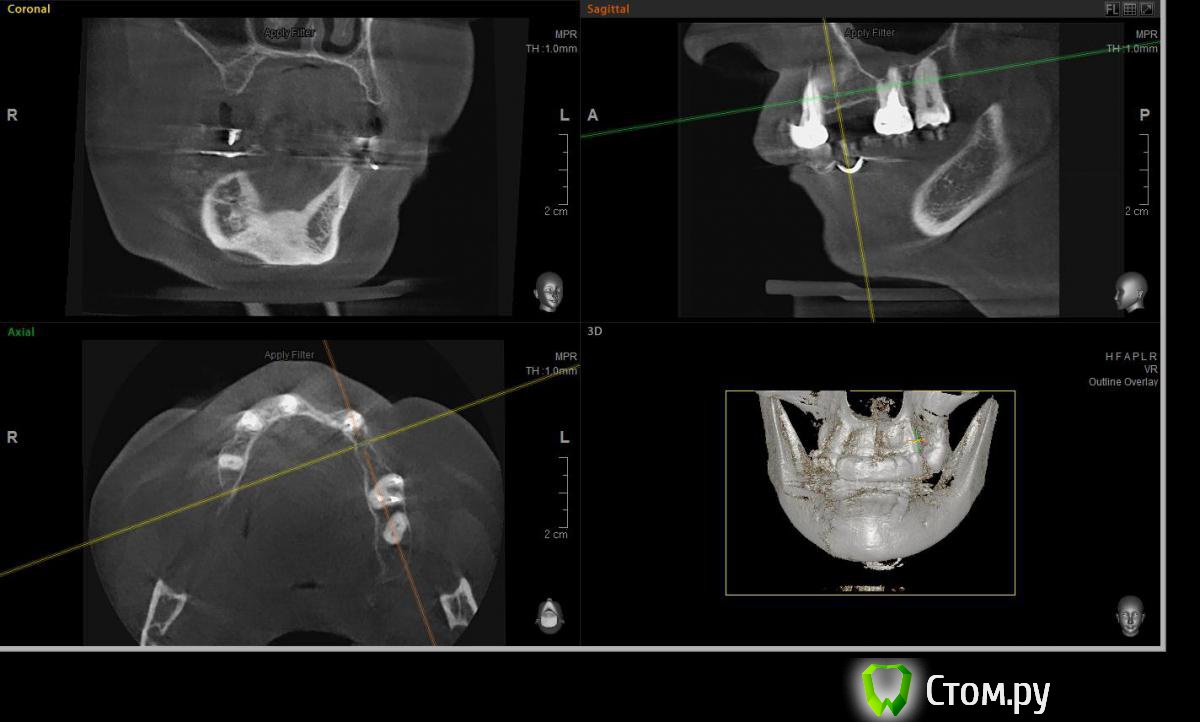

Евгений Ходыкин Опубликовано 23 июля, 2014 Поделиться Опубликовано 23 июля, 2014 Решили с пациенткой пока начать с в.ч. В планах имплантация в область отсутствующих 1.6, 1.4, 1.2, 2.1, 2.2, 2.4, 2.5. С 1.6 самому более менее все понятно, мануальных навыков хватит) Прошу помощи коллег относительно остальных областей. Фронт особливо печален... Забегая наперед скажу, что блоки еще не делал. Ауто точно пока брать не планирую, ибо нет даже теоретических навыков. Хочу начать все-таки с аллоблоков. У кого какие будут мнения, заранее спасибо) Ссылка на комментарий

Sahan Опубликовано 23 июля, 2014 Поделиться Опубликовано 23 июля, 2014 вот всё хочу сетку попробовать в похожем случае, но каждый раз нахожу повод сделать по другому, даже небольшая вероятность оголения не по душеОголение сетки не так страшно как оголение цитопласта. Тем более Вы же начали использовать мукодерм, какое ж тут оголение))). В случае топик-стартера требуется наращивание и небно и вестибулярно. Поэтому прийдется хорошо тянуть лоскут. Я в таких случаях в первый этап наращиваю кость вестибулярно блоком, а во втором этапево время имплантации с небной стороны ставлю сетку плюс ССТ. Ссылка на комментарий

Rafael_Gogyan Опубликовано 24 июля, 2014 Поделиться Опубликовано 24 июля, 2014 (изменено) фронт блоклибо сосиску (минимум 50% ауто) с одномоментной имплантациейв боковых отделах особых проблем не вижу. имплантация с НТР в обеих случаях + ССТ на ножке с нёба Изменено 24 июля, 2014 пользователем Rafael_Gogyan Ссылка на комментарий